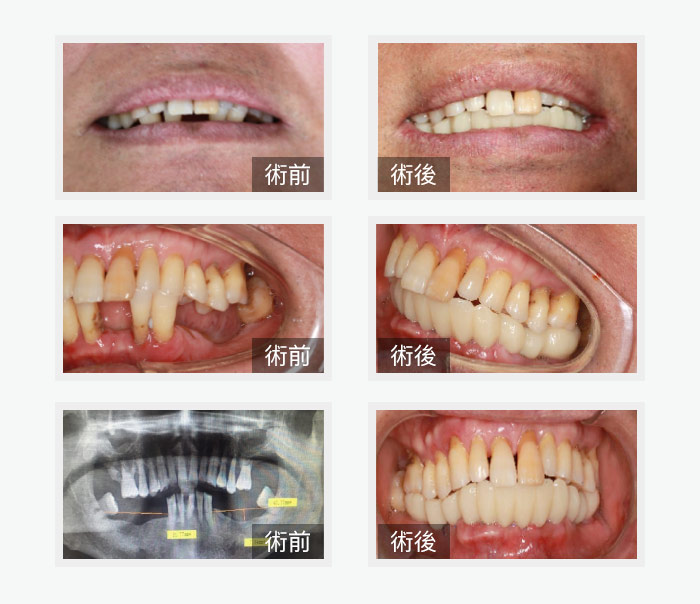

真實案例展示區